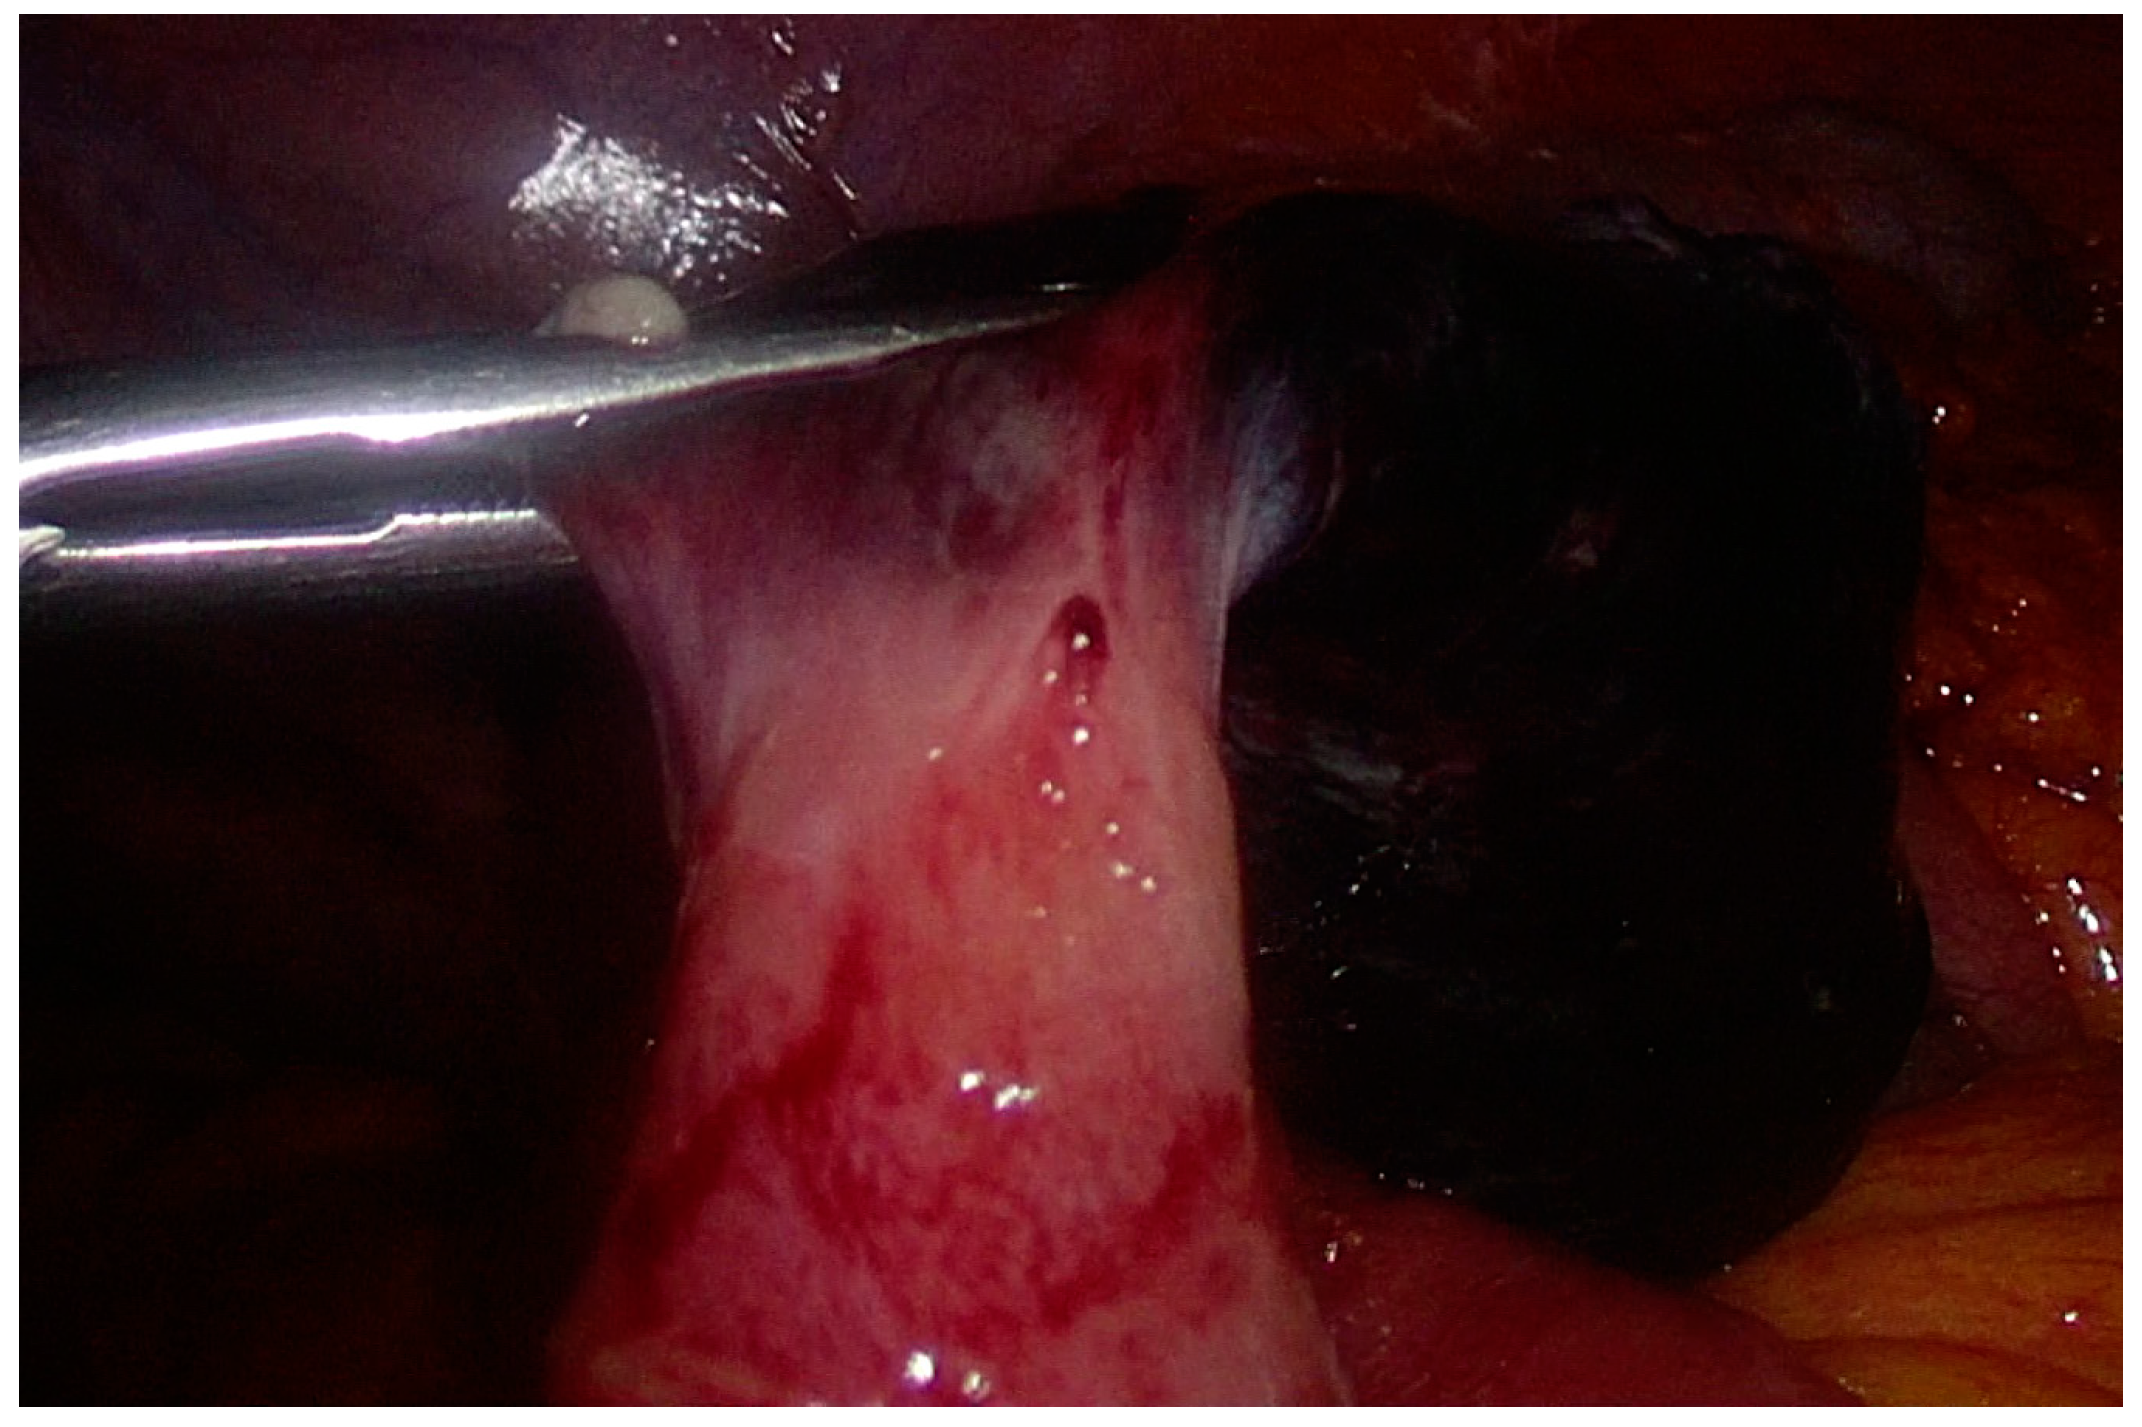

2. Case Presentation